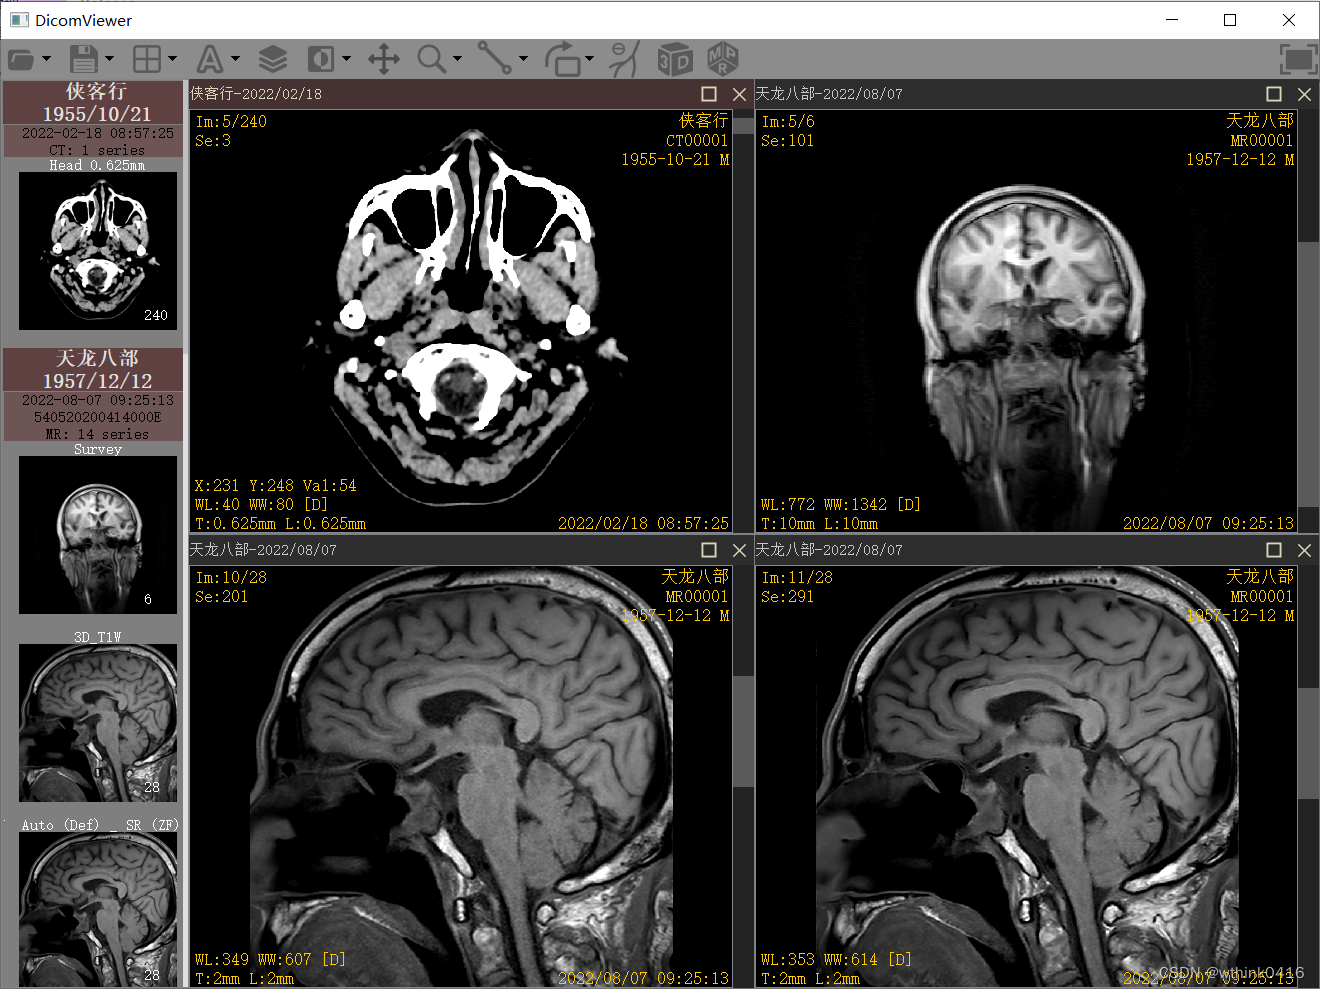

首先是主界面,上面是工具栏,左侧是序列的缩略图部分,右侧是图像展示部分

1、首先选择工具栏文件夹标,分为打开文件和打开文件夹,并设置了指定的快捷键,选择两组数组打开分别为一个CT检查和一个MR检查,显示后,支持鼠标拖拽序列到指定窗口。

2、选择工具栏的分格图标,可以对图像显示区域进行调整,在每个图像窗口中双击可以实现最大化和还原